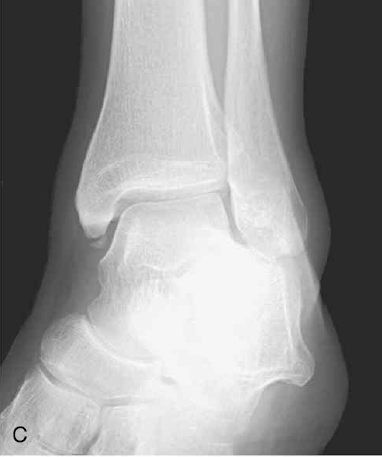

B는 Maisonneuve 골절로, 골간막의 파열과 비골 상단 1/3 부위의 골절을 나타낸다.

C는 Maisonneuve 골절로, 내측 복사뼈 골절 동반된 사진이다.